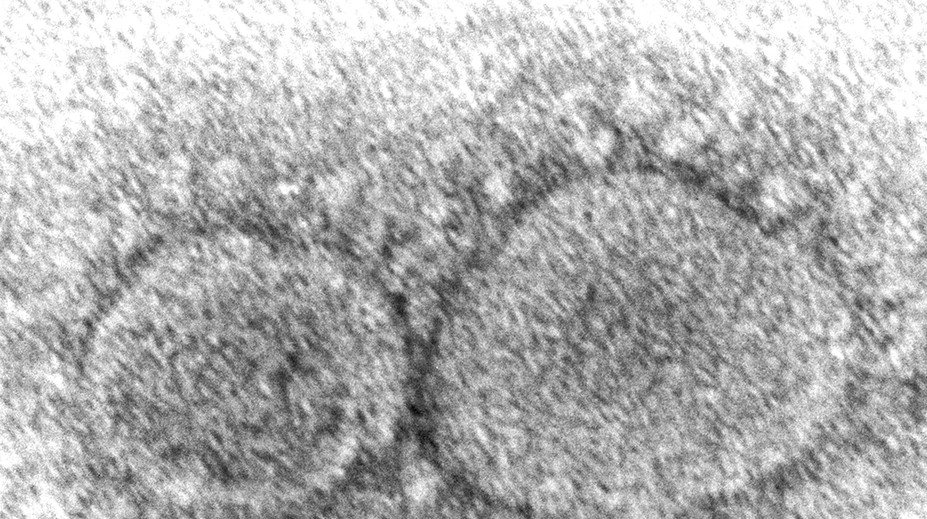

Vedci prišli s doteraz najsilnejším dôkazom o tom, že pandémiu koronavírusu spustilo zviera TASR 17. 3. 2023